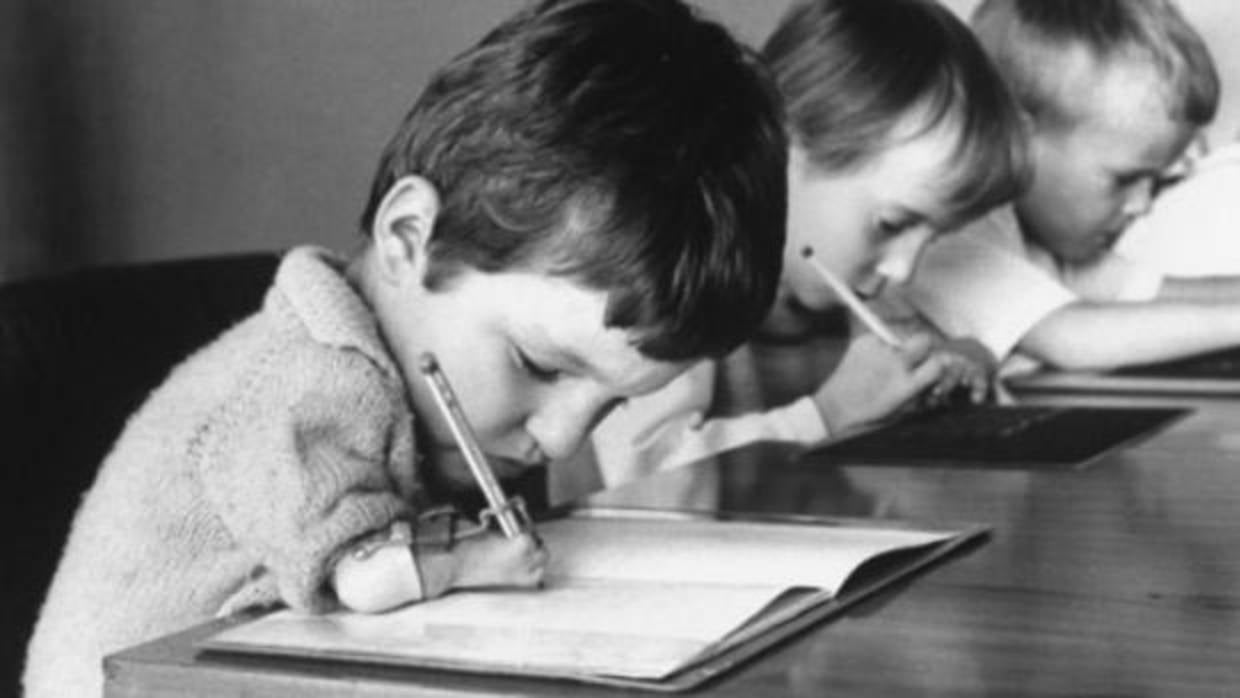

Fueron al menos 10.000 niños que nacieron con diferentes malformaciones. Algunos sin brazos, otros sin piernas.

Se teme que muchos otros murieron en el útero.

“Muchos de los que se tomaron la medicina, incluyendo un número alto de niños, sufrieron de una muerte agonizante”, recordó el periódico estadounidense.

Esta foto de 1968 muestra a la niña Barbie Hanavan, cuando tenía 6 años. Ella fue una de las víctimas de la talidomida cuya historia fue dada a conocer por la prensa de la época.

Miles de niños de más de 45 países sufrieron malformaciones después de que sus madres ingirieran talidomida en el embarazo.

Se reportaron malformaciones cardíacas, auditivas, gastrointestinales y en las extremidades de los bebés.

En 1956 se documentó el primer caso aislado de focomelia tras la exposición a talidomida y en los 5 años posteriores se registraron en todo el mundo aproximadamente 3.000 dismelias, malformaciones congénitas extremadamente infrecuentes en los miembros, tales como amelia (ausencia de todo el miembro), focomelia (pérdida o acortamiento grave de los elementos proximales) y ausencia/hipoplasia del pulgar o los dedos, entre otros.

Durante esos años, se detectó un aumento progresivo de casos de malformaciones congénitas, con una mortalidad del 40% durante el primer año de vida, que no se limitaban exclusivamente a la afectación de las extremidades, sino que se asociaban también a alteraciones cardíacas, renales, digestivas, oftálmicas y auditivas.

Aunque la cifra de afectados a nivel mundial no se conoce con exactitud, se ha estimado la existencia de más de 10.000 recién nacidos con malformaciones durante el periodo de comercialización de la talidomida.